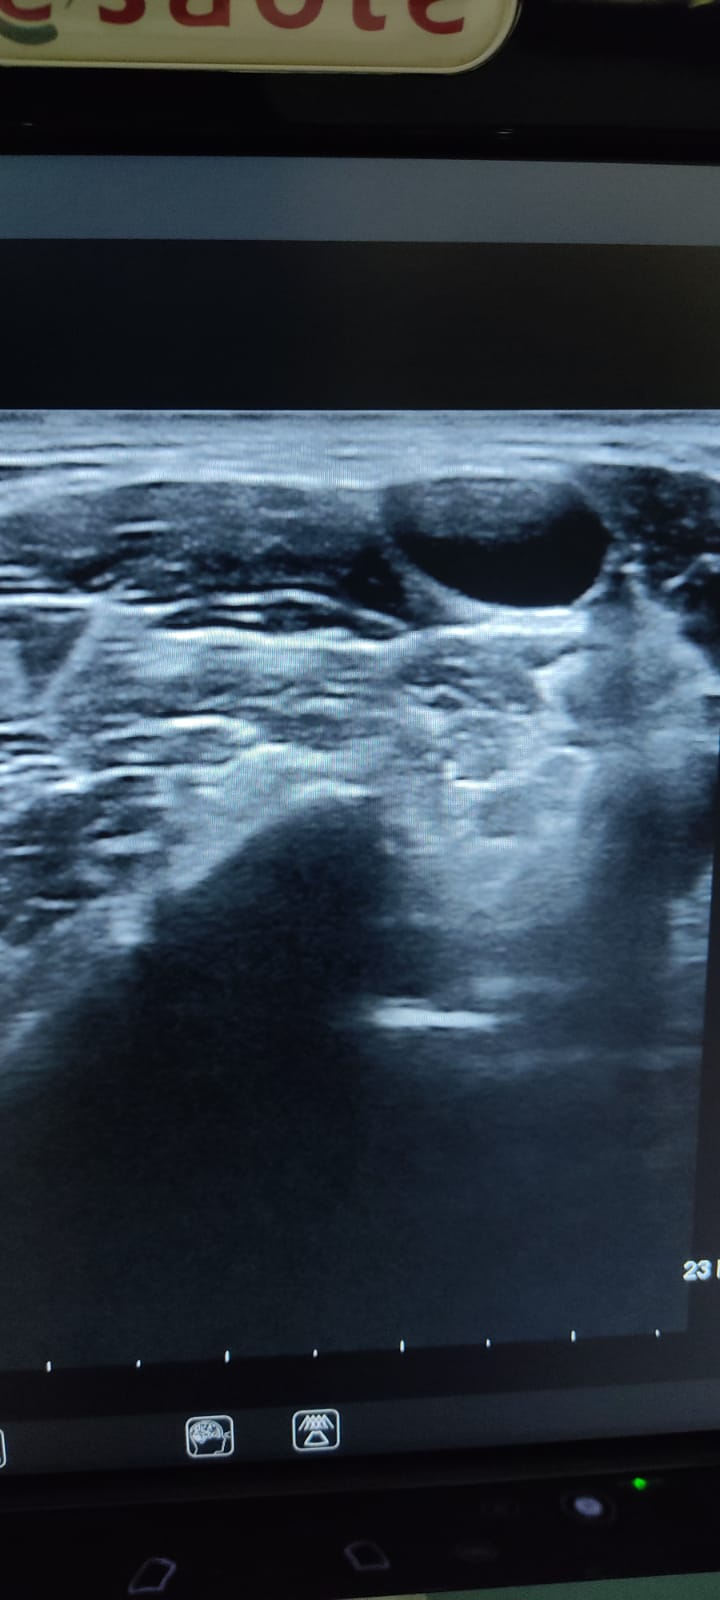

Se le realiza una Ecografía clínica a pie de cama (POCUS), donde se observan múltiples adenopatías anecoicas en ambas cadenas submandibulares y laterocervicales, algunas de 3 cm aproximadamente, de aspecto redondeado y con sugestiva presencia de hilio.

En LTI, se observa nódulo espongiforme en su parte superior sólido con calcificaciones en región inferior de más de 2 cm de diámetro superior, más alto que ancho con calcificaciones groseras, presentando otro nódulo de similares características en cara posterior de LTD. Todo ello, es sugestivo de TIRADS 5.